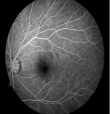

3.png

正常眼底造影

4.png

早期糖网-血管瘤样改变